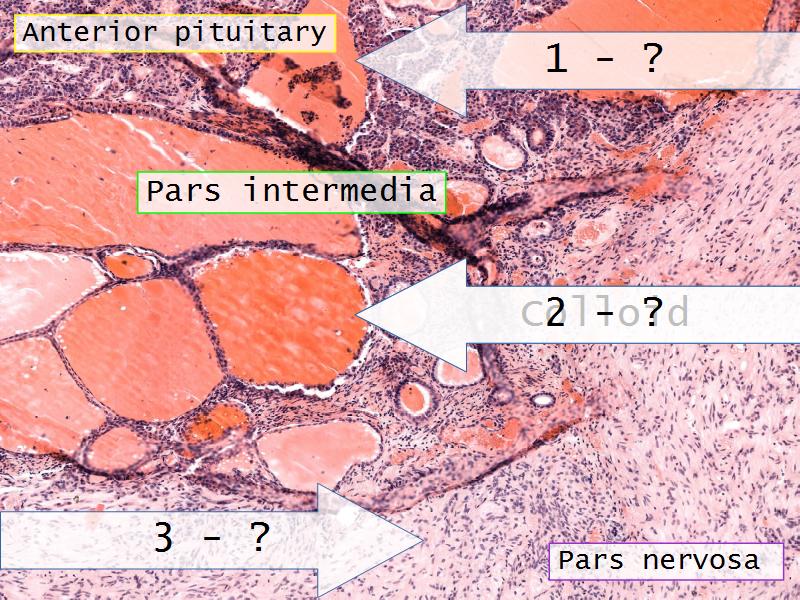

- Slide 52: Pituitary gland

Pituitary gland

How does the pituitary and hypothalamus communicate?2 ways